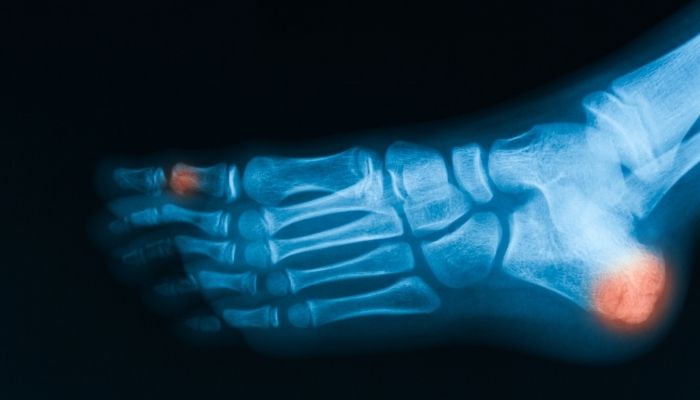

- X-Rays: an X-ray will confirm whether you have an oblique fracture or other types of fractures. An X-ray will also confirm how your injured bones are.